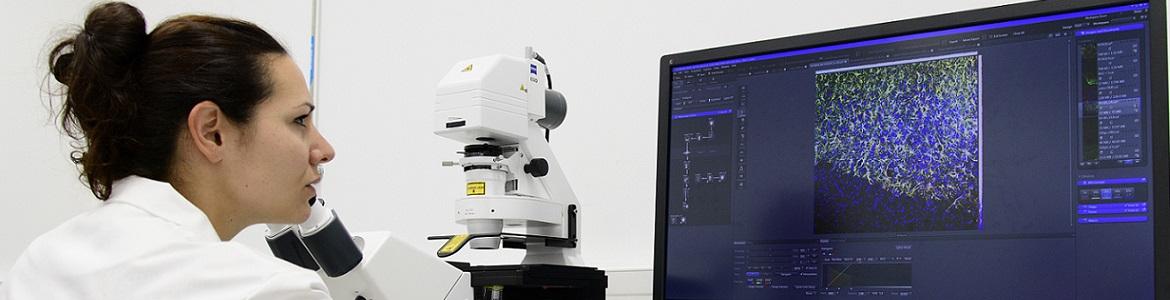

Embarquez pour un voyage immersif à l’intérieur du cerveau ! Entre faisceaux de neurones et vaisseaux sanguins, visualisés en 3 dimensions, découvrez comment une nouvelle méthode d’imagerie médicale contribue à la recherche sur les maladies neurologiques. Les rayons X produits par un accélérateur de particules, le synchrotron, permettent de réaliser une dissection virtuelle, et fournissent de fabuleuses images du cerveau.